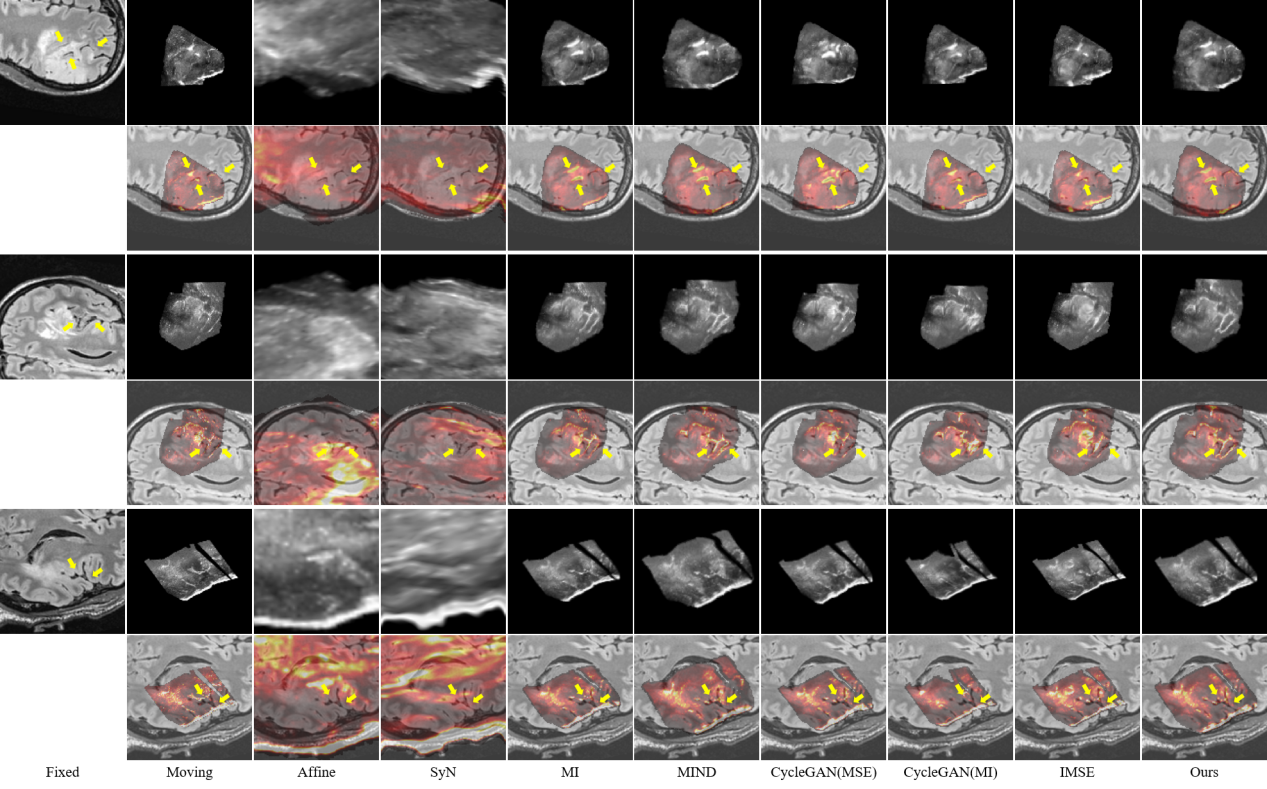

研究结果表明,SynMSE 在L2R 2022 CT-MR腹部数据集、临床宫颈CT-MR数据集以及CuRIOUS MR-US脑数据集上均取得了最优配准性能。与传统方法相比,SynMSE显著提升了Dice系数、降低了HD95与TRE误差,实现了在复杂模态差异下的高精度解剖结构对齐。图4-图6分别为所提出方法在三个数据集上的定性结果展示,红色标注代表固定图像的目标器官区域,黄色标注代表浮动图像与配准后图像的目标器官区域。表示图中结果显示,SynMSE更好的克服了多模态图像间的复杂分布差异,不仅实现了更精确的配准效果,而且有效保持了组织边界与解剖拓扑的完整性,明显优于现有方法。

图6:所提出方法与现有方法在CuRIOUS MR-US脑数据集上的定性效果(黄色箭头指向图像上的较为明显的脑沟等显著结构